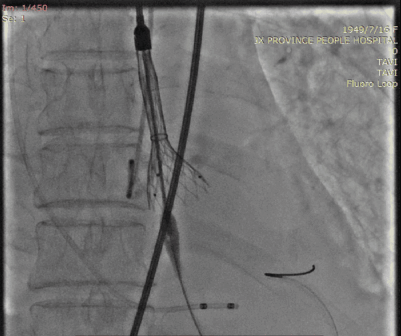

稍高位释放

稍高位释放,释放过程中略微下移。

瓣膜展开后可见接近标准位,且无瓣周漏。

5月19日,朱奶奶被送入介入室行经导管主动脉瓣置换术,由于下肢血管入路极度扭曲,并且低血压,难以耐受长时间麻醉及手术,洪浪院长团队简化方式建立入路,再进行全麻,并迅速完成垮瓣、球囊扩张及Venus A 26mm瓣膜释放,术后造影提示瓣膜位置良好,无瓣周漏,左心室与主动脉压差从术前139mmHg降至7mmHg,手术非常成功。从病人上台至股动脉缝合共耗时100分钟,术后转入CCU进行复苏,继续监测生命体征。